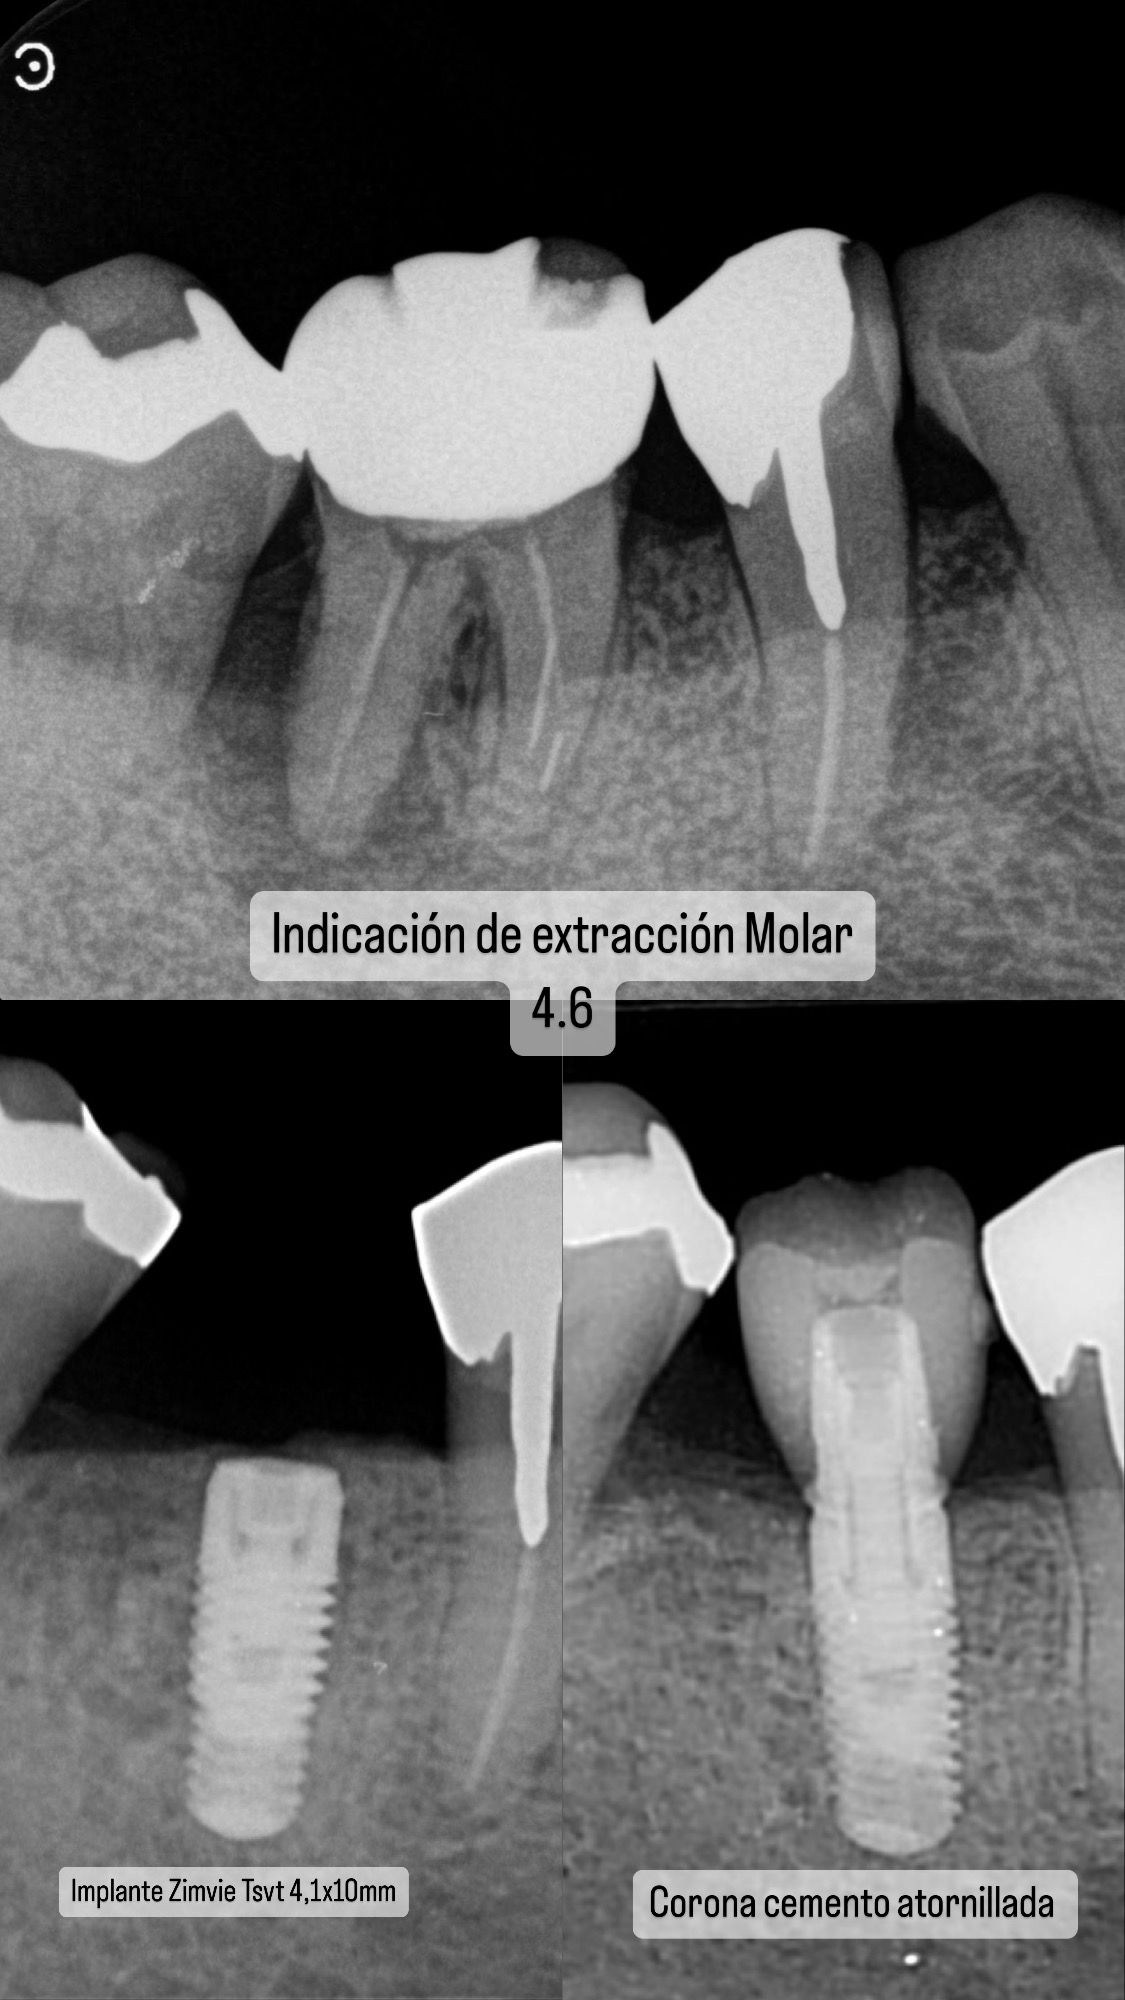

Diseño de Sonrisa con Implantes y Rehabilitación Oral

Descripción del caso:

Paciente tratado con cirugía de implante dental, finalizado con rehabilitación oral completa mediante coronas cerámicas y carillas estéticas, logrando un cambio integral en función y estética.

Procedimiento realizado en su totalidad por el Dr. Axel Paredes.